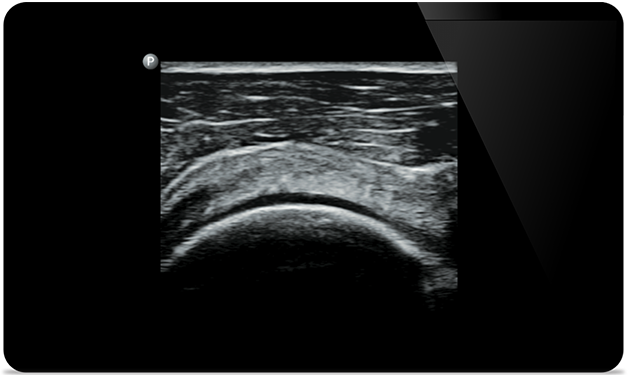

Lumify helps you see the fine details in muscles, joints, ligaments, tendons and cartilage to make a more accurate diagnosis of injuries.

Lumify can help you assess patients from head to toe, whether it’s plantar fasciitis, tendonitis or bursitis in the patellar tendon, or even shoulder instability in the rotator cuff.

SonoCT reinforces real tissue imaging while eliminating random artifacts. This technology produces images superior to conventional imaging in up to 94% of patients.